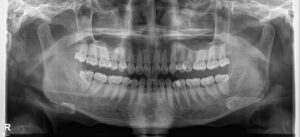

Kết quả phân tích phim mặt nghiêng cephalometric: Sai hình xương hạng II, cằm có xu hướng ra trước , cắn sâu khung xương.

Kế hoạch điều trị: Nhổ 2 răng số 4 hàm trên, đóng khoảng bằng chun cuối, giải quyết khớp cắn sâu bằng cách đánh lún nhóm răng cửa và làm trồi nhóm răng hàm. Sử dụng T- loop SS 17×25 ở hàm dưới để đánh lún ở giai đoạn cuối.